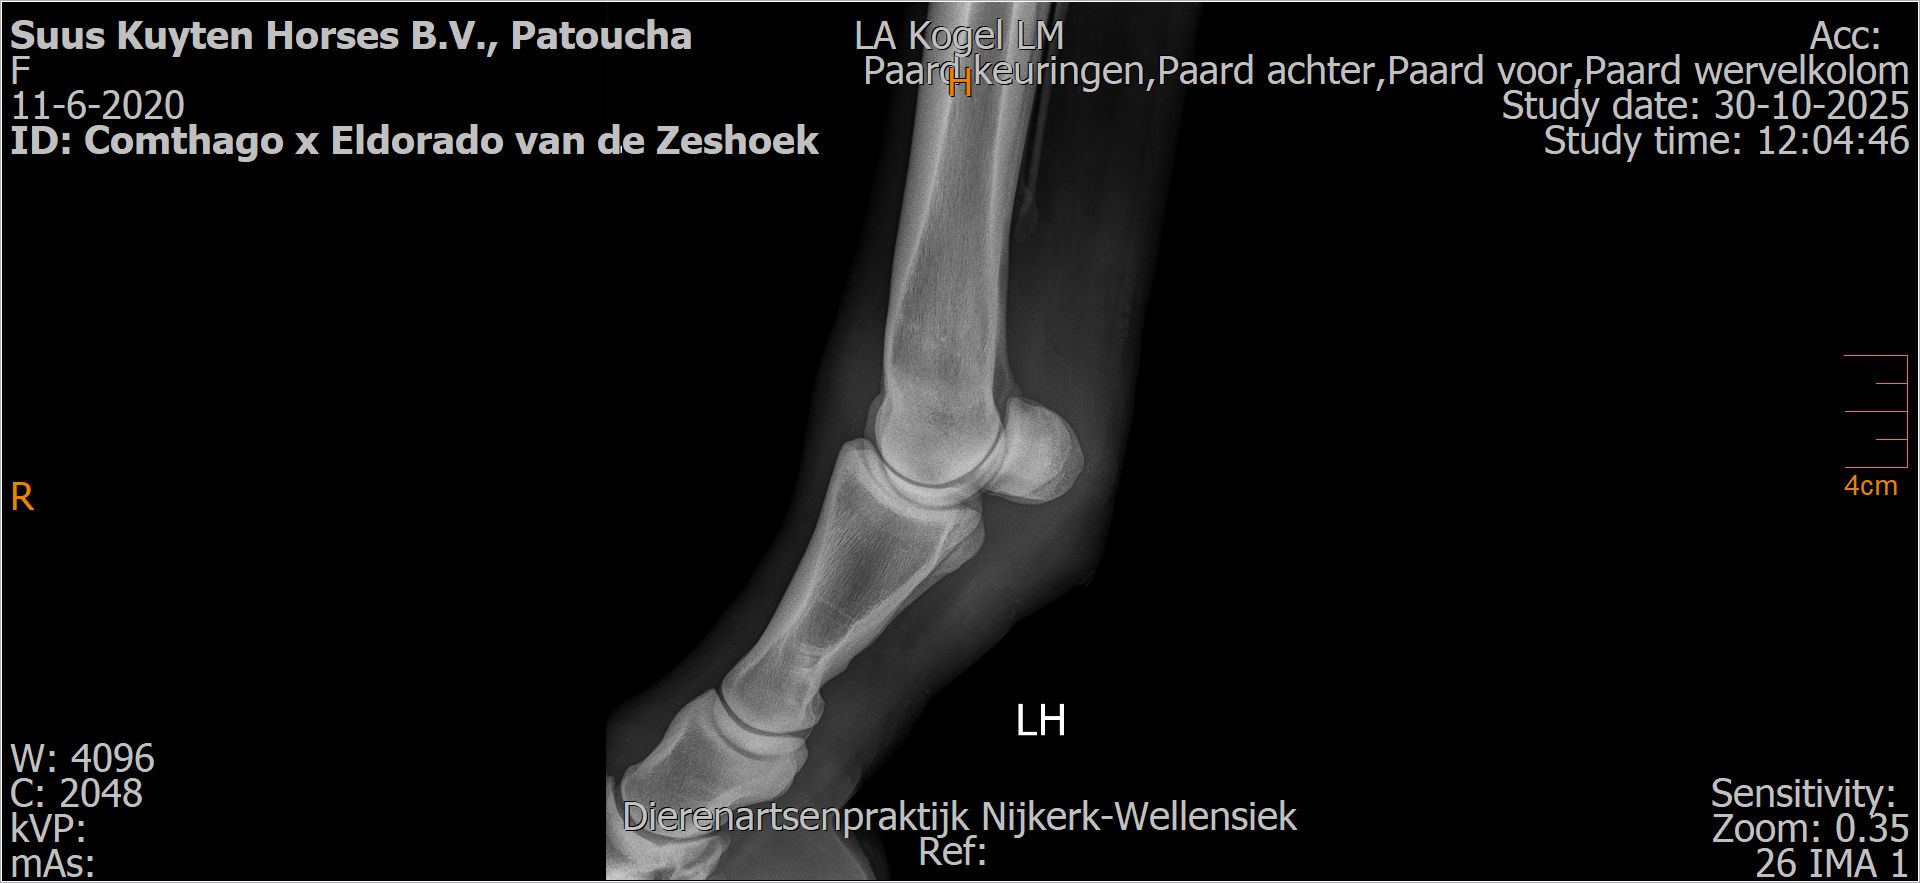

Patoucha

Leeftijd:

7

Röntgenfoto’s